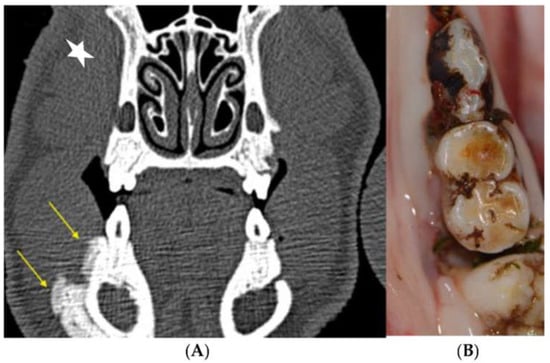

3.2.1. Clinical Evaluation

3.2.2. Histological Evaluation

3.2.3. Radiological Evaluation